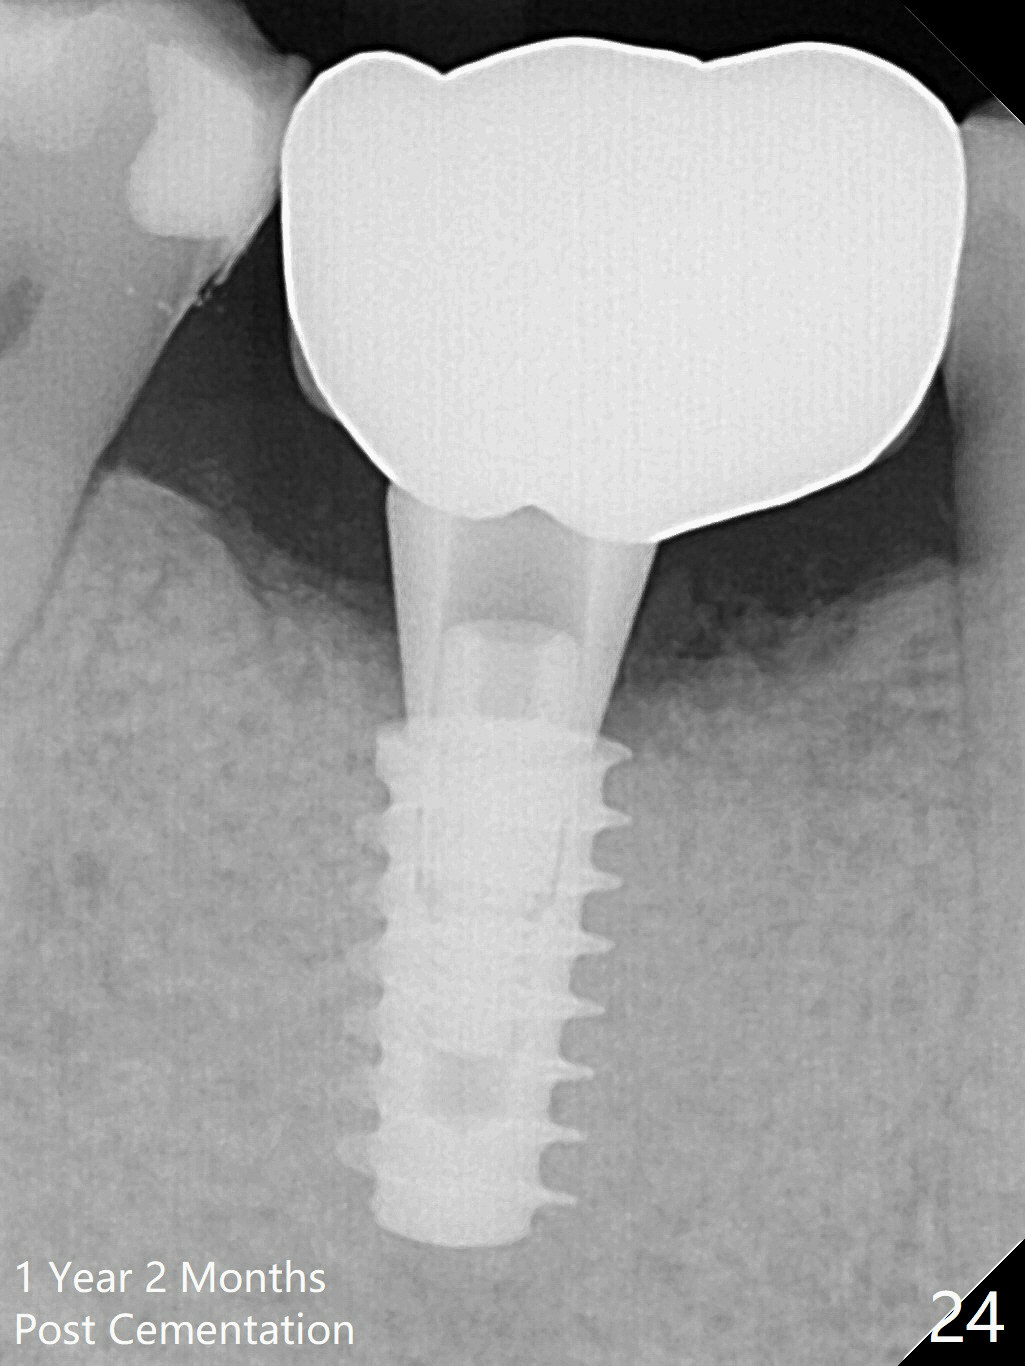

Three weeks later (5.5 months postop), a permanent crown tries in with healthy keratinized gingiva (Fig.18). The provisional keeps normal gingival bed (Fig.19), while the abutment forms tissue cuff (Fig.20). After cementation, PA shows bone regeneration (Fig.21). The gingiva remains healthy 8.5 months post cementation (Fig.22). Bone density around the implant increases 1 year 2 months post cementation (Fig.24). The gingiva remains healthy 2 years 4 months post cementation (Fig.25).